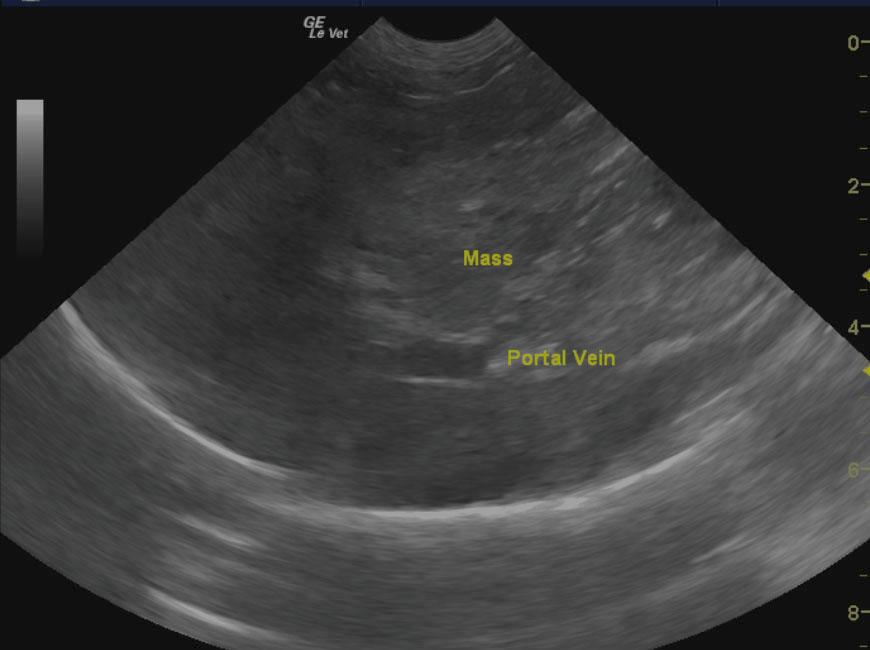

Left sided liver mass extending to the right side and dorsally into the diaphragm enveloping the vena cava. This is not overtly resectable. FNAs were performed on the mass itself without evidence of complication. This is likely hepatocellular carcinoma or similar neoplasia. Poor long term prognosis.

The liver in this patient presented an 8.8 x 7.6 cm, mixed, hyperechoic nodular mass with areas of capsular expansion and reactive surrounding omentum. Microaccumulation of fluid was noted within the mass as well. It appeared to derive from the left liver and extend into the deep left liver enveloping the cranial aspect of the gallbladder and separate nodular changes were noted in the right liver in the region from the vena cava inlet through the diaphragm. Loss of architecture was noted throughout this region. The gallbladder revealed a minor amount of dependent debris. The mass appeared to impinge upon the portal vein from the left side with nodular changes on the right side are suspected as well.